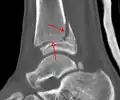

A triplane fracture of the ankle as seen on CT -

A triplane fracture of the ankle as seen on CT

CT

CT scans may be indicated when there is concern for a highly comminuted fracture or a fracture involving the joint surface.[10] This imaging may be used for surgical planning.